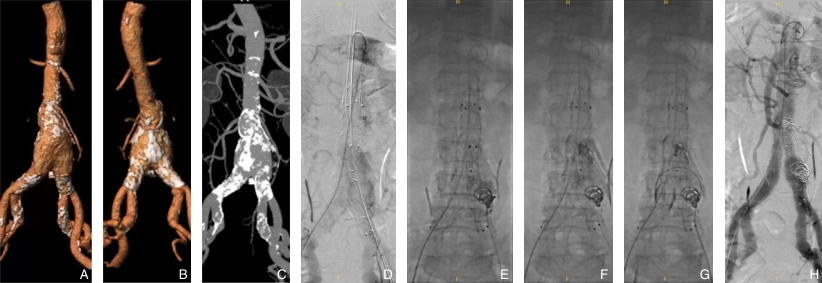

图2 术中Ⅰ b、Ⅱ型内漏的处理 A-C:术前CTA可见瘤颈条件良好,但存在粗大肠系膜下动脉与腰动脉,且双侧髂总动脉明显钙化,提示术中Ⅰb与Ⅱ型内漏风险高;D:术中造影可见双侧Ⅰb和来源于腰动脉的Ⅱ型内漏明显;E-G:分别选择性栓塞左侧Ⅰb内漏、腰动脉来源Ⅱ型内漏、右侧Ⅰb型内漏;H:最终造影见所有内漏均消失Fig.2 Intraoperative management of type Ib and type Ⅱ endoleaks A-C: Preoperative CTA demonstrates favorable proximal neck anatomy, but reveals a prominent inferior mesenteric artery and lumbar artery, as well as significant calcification of both common iliac arteries, suggesting a high risk for intraoperative type Ib and type Ⅱ endoleaks; D: Intraoperative angiography shows evident bilateral type Ib endoleaks and a type Ⅱ endoleak originating from lumbar arteries; E-G: Selective embolization is performed for the left type Ib endoleak, the lumbar artery-derived type Ⅱ endoleak , and the right type Ib endoleak, respectively; H: Final angiography confirms complete resolution of all endoleaks